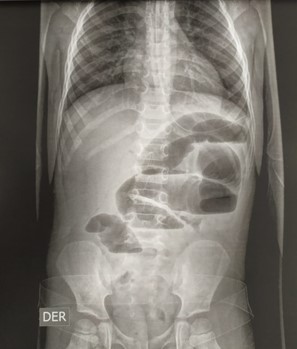

Intususcepción secundaria a divertículo de Meckel. reporte de caso

Luis Roberto Hernández Mercado, Sergio Iván Granados Torres, Joaquín Enrique Villamizar Zúñiga

Diverticulitis en colon sigmoides de una niña de 9 años. Reporte de caso

José Alfredo González-Ortiz, Luis Enrique Toxqui-Merchant